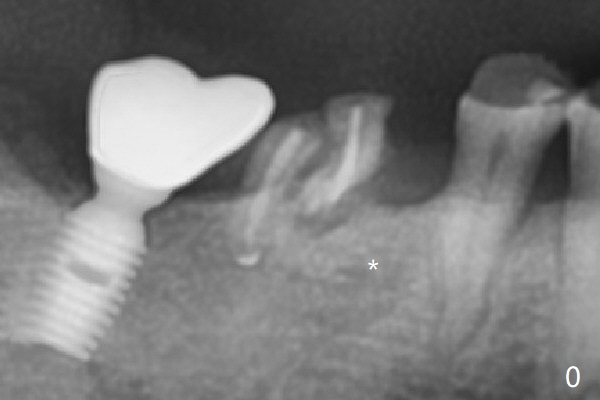

Vertical fracture of the mesial root of the tooth #30 after RCT is associated with bone loss (Fig.00 *). When the mesial portion of the mesial root (M', loose one) is exfoliated, the bone loss resolves (Fig.0). To reduce heat-induced bone necrosis at #19, osteotomy is conducted slowly with copious irrigation with cold saline. Bone density is felt while a 5x10 mm implant is being placed after using cortical tap to the 2nd line of the implant driver. The implant needs to be reverse torqued several times before reaching its final depth (Fig.1 (~50 Ncm)). Since the residual roots are superficially positioned, the immediate implant looks as a delayed one. Although the implant is placed mesial to the septum clinically, its position in X-ray seems to be normal. Because of severe wear and lack of vertical height, a 6.8x5 mm healing abutment is placed. Retention of bone graft (Fig.1 *) is maintained by spreading setting acrylic into the edentulous undercut areas (Fig.2 *). The so called "acrylic dressing" remains in place 3 weeks postop (Fig.8). When it is removed with the healing abutment, the wound heals (Fig.3). Note the limited vertical height. The bone graft placed in the distal socket appears to have been converted to the native bone 3.5 months postop (Fig.4). To reduce severe wear of the natural teeth, the occlusion of the new crown is not heavily decreased (Fig.5). It should be alright considering favorable crown/implant ratio (Fig.6). There is no bone loss 5 months post cementation, although the abutment screw is just retightened (Fig.7). In spite of poor trajectory associated with #18 (Fig.8) and 31 (Fig.7) Bicon implants, the abutments have not been dislodged. For the bruxer, the next implant at #19 with distal root fracture (Fig.8 ^) should be Bicon. The patient complains of food impaction nearly 1 year post cementation. The mesial and distal contacts of #30 crowns are light. When the abutment/crown is removed, there is implant well contamination (food debris). It appears that the previous abutment (5.7x4(2) mm, Fig.6,7) is incompletely seated. When a smaller abutment is placed and torqued at 30 Ncm, it is seated fully (Fig.9 (<: no gap)). New impression is taken. The distal gingival embrasure is larger than the mesial one because of the higher distal crest (Fig.6,7). If there is food impaction distal to the new crown, the distal crestal bone should be removed with lab closure of the embrasure.